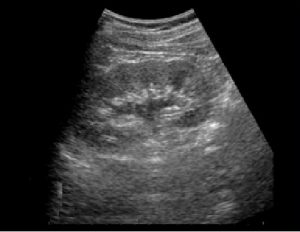

Amazon.co.jp: Nikkei メディカルビデオ VOL.50 30分でわかる, 腹部エコー|医療法人 さわい消化器クリニック|大腸カメラ・胃,

腹部エコー|医療法人 さわい消化器クリニック|大腸カメラ・胃, m3電子書籍 | 正常画像と並べてわかる腹部エコー,

m3電子書籍 | 正常画像と並べてわかる腹部エコー, Liver | GE HealthCare (Japan),

Liver | GE HealthCare (Japan), 設備紹介 | 施設紹介 | メディカルクリニック武蔵境